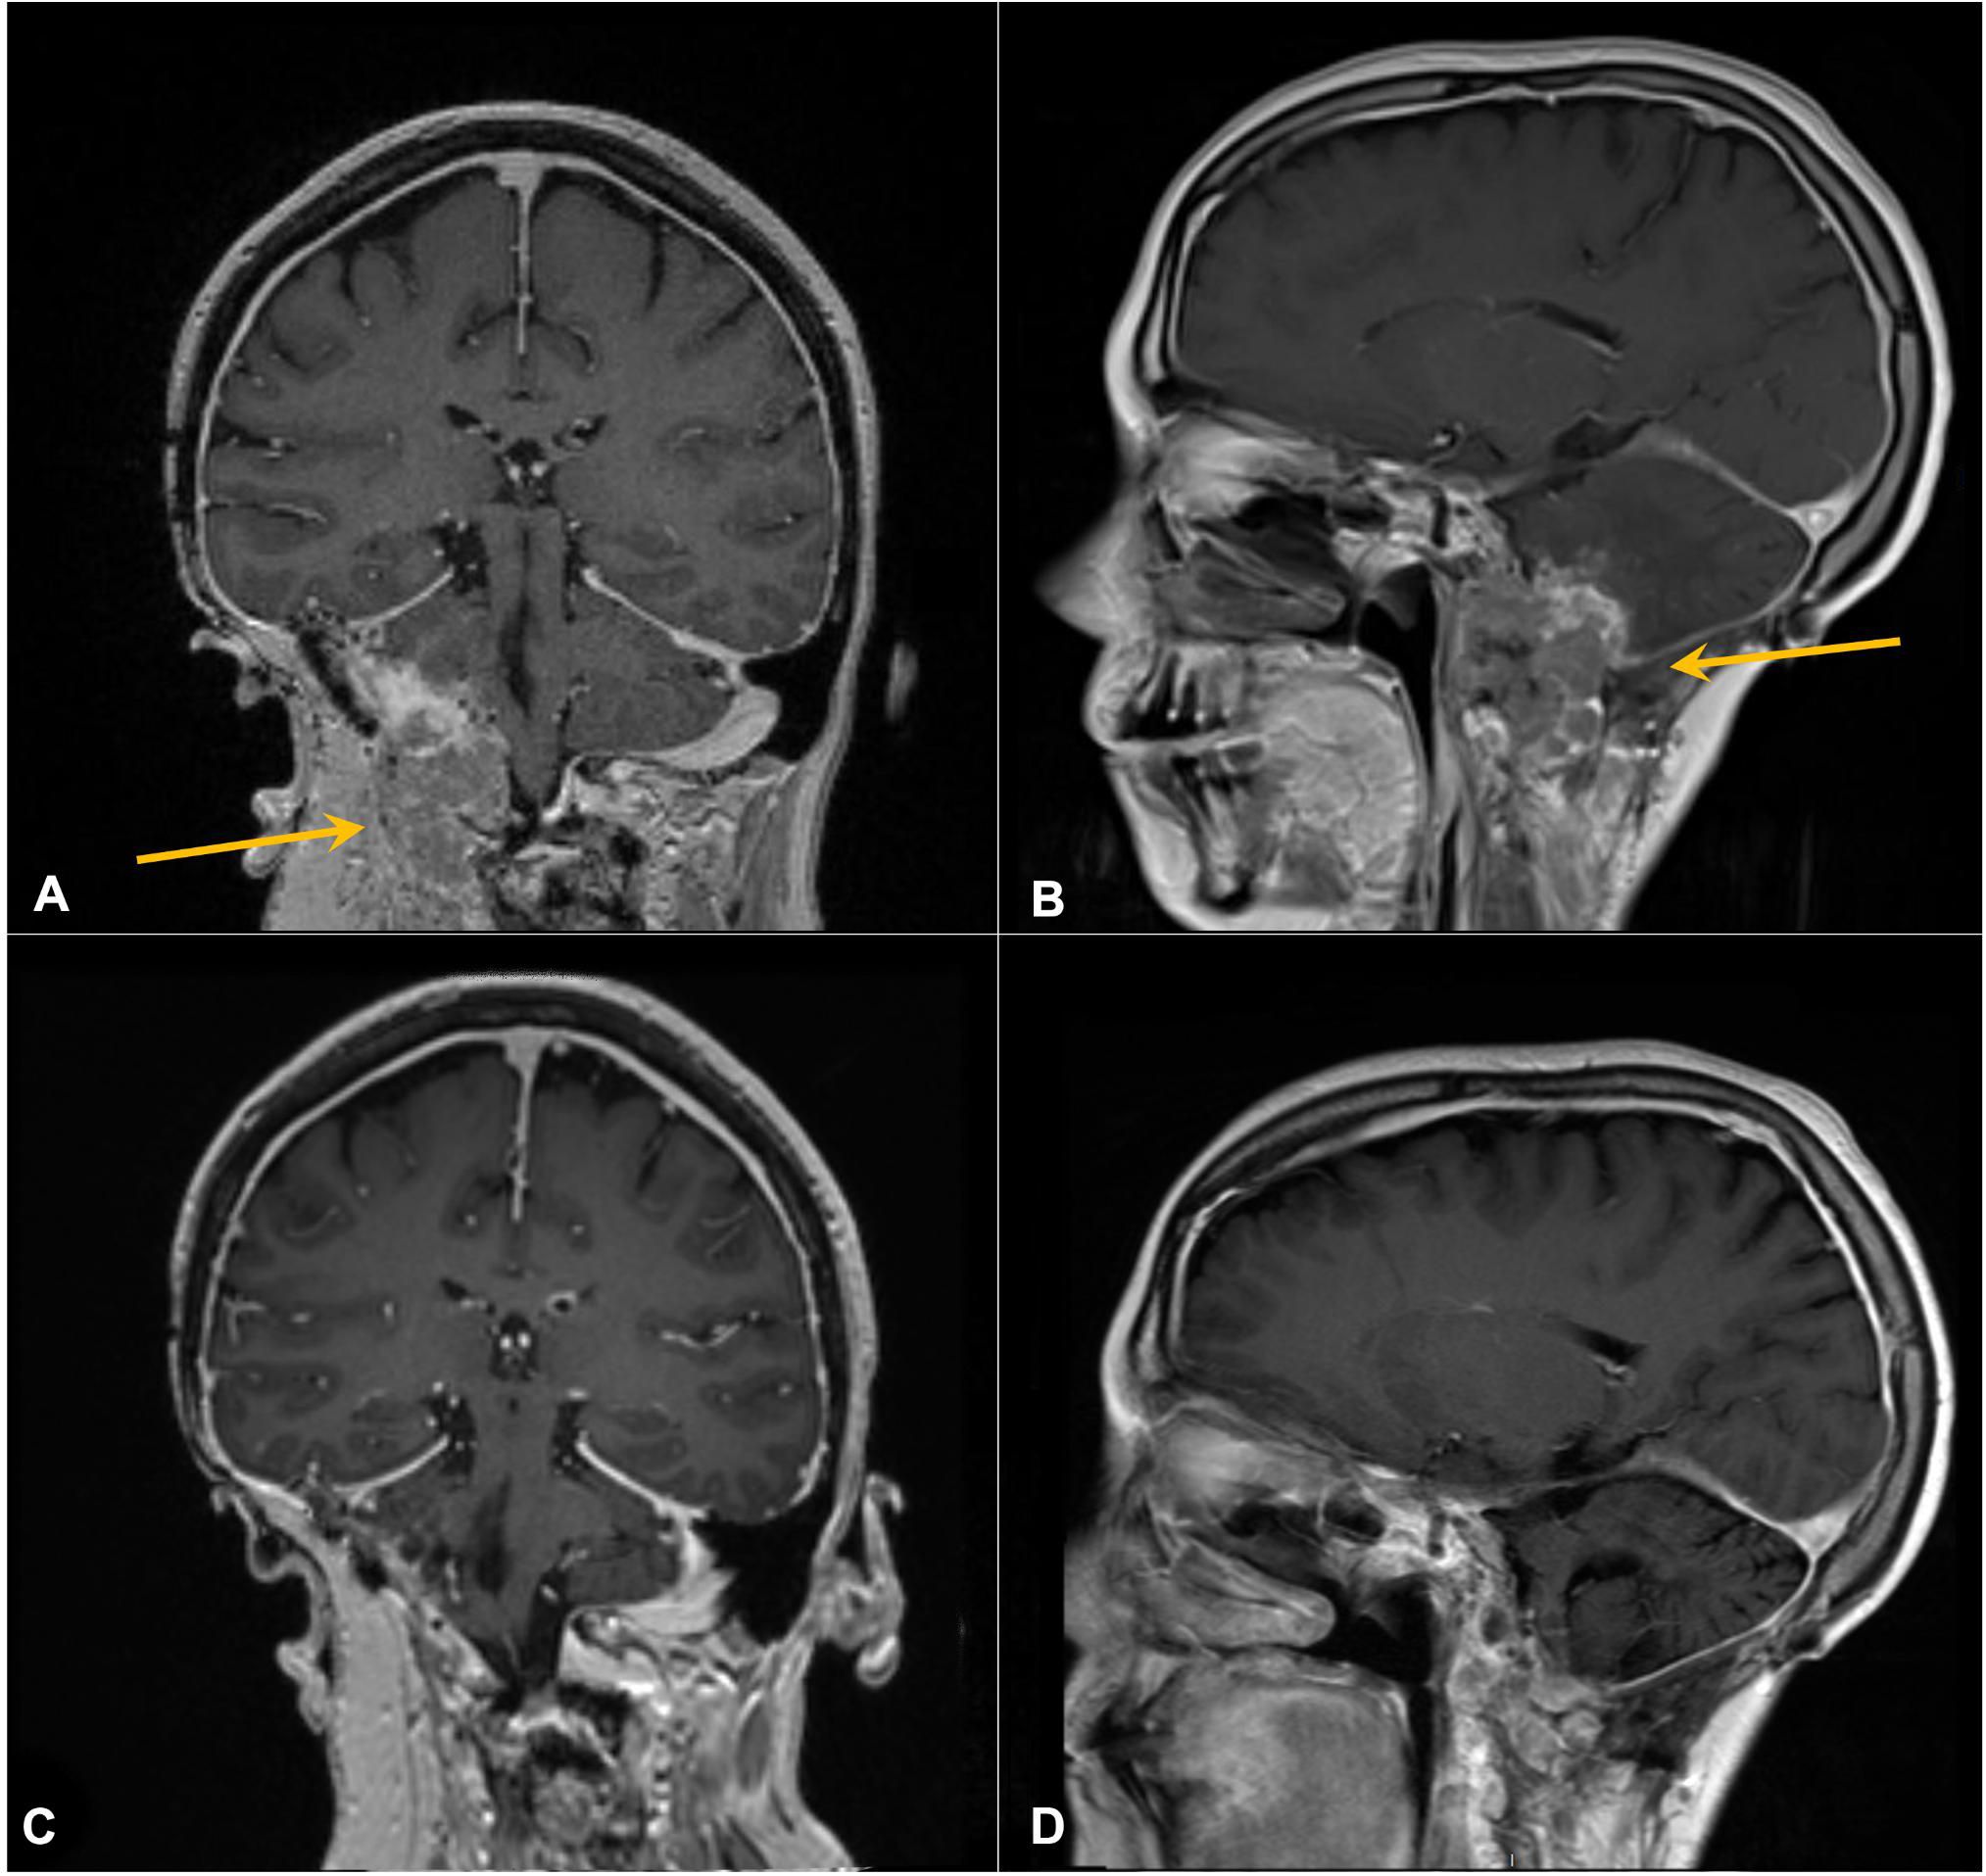

Having the PBRM1 mutation, a mutation possibly associated with immune therapy response in RCC, pembrolizumab was administered at standard flat dosing of 200 mg every 3 weeks starting in September 2019 (30 months from R1). The patient soon reported improvement in her symptoms and, after three cycles, returned to full-time work. She experienced no significant adverse effects from therapy. Repeat imaging demonstrated a reduction in size with near resolution of mass effect (Figures 4A, B), and she continued ICI therapy. At the time of manuscript writing, the patient had completed 66 cycles of pembrolizumab 200 mg every 3 weeks since R2. She continues to work and enjoys high performance status and has no evidence of disease on her most recent imaging (Figures 4C, D), approximately 3 years 9 months from the initiation of ICI therapy and 50 months from R2.

MRI images show brain scans in four panels labeled A through D. Panel A is a coronal view with an arrow indicating an abnormality. Panel B is a sagittal view also with an arrow pointing to an area of interest. Panels C and D show similar views without annotations.

Figure 4. Contrast-enhanced coronal (A, C) and sagittal (B, D) T1 MRI of the brain. Arrows in panels A and B mark enhancing right cerebellar/skull base prior to pembrolizumab. (C, D) Following six cycles of therapy, demonstrating response.